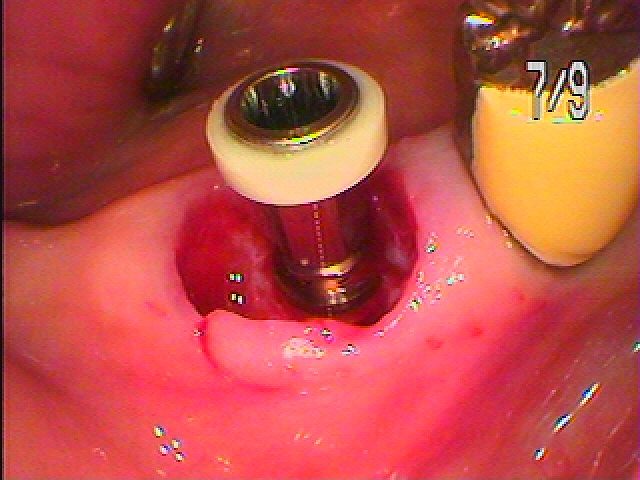

このように5㎜の13㎜というインプラントを埋入しています

隙間には像骨処置として骨補填材を敷き詰めています

このように埋入しています